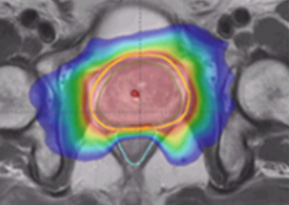

Example of older-style treatment

Example of newer-style treatment